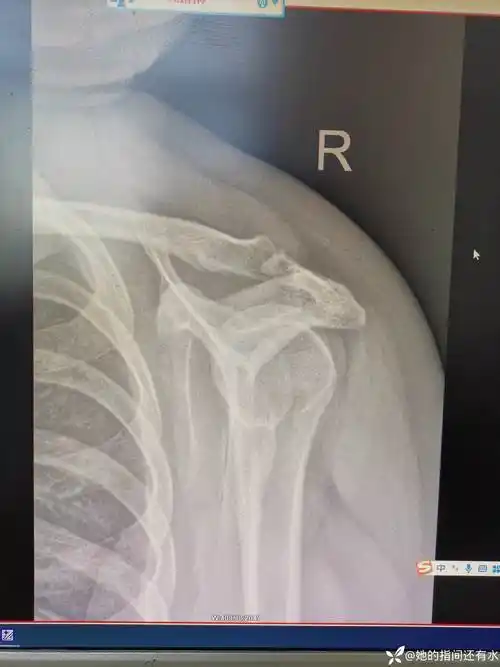

肩关节半脱位